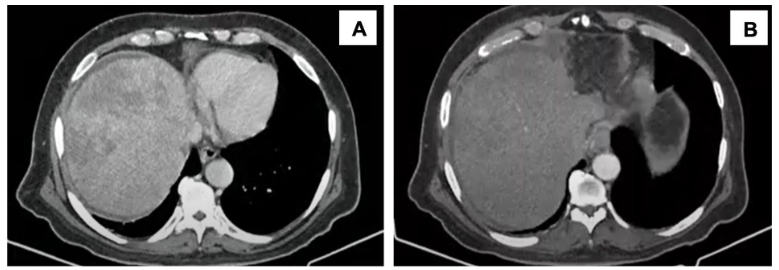

入院实验室检查显示肝酶轻度升高。腹部多期增强CT显示肝脏有一巨大异质性肿块,伴有腹水、多发淋巴结肿大及慢性门静脉血栓形成(图1)。胸部CT显示淋巴周围分布有结节。

图 1.(A)动脉期腹部 CT 和(B)门静脉期显示出现大范围且外观异质的肝脏肿块